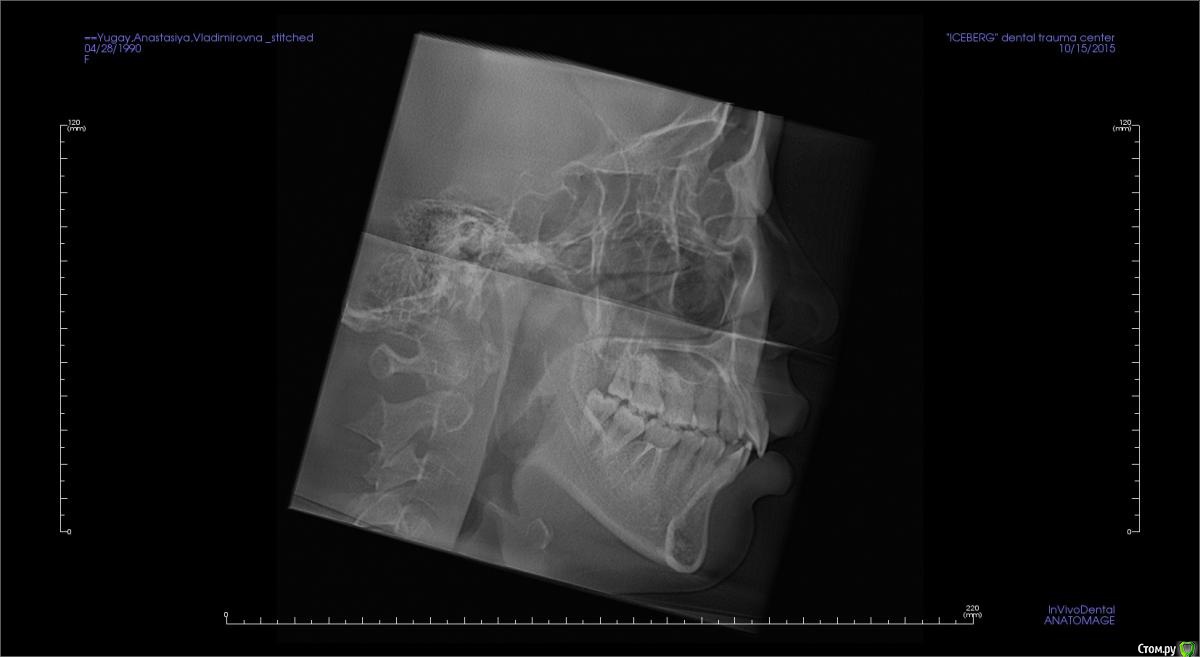

Головные боли, артроз ВНЧС, дистальный глубокий прикус, удалены 4ки на вч и 5 на нч

Сейчас мне 25 лет. С детства был дистальный глубокий прикус, зубы на верхней челюсти выпирали вперед, на нижней челюсти присутствовала скученность, из-за чего была удалена "мешающая" 5ка. Вероятно, этот зуб стоило сохранить.

В 2007-2008 гг. проходила ортодонтическое лечение с удалением 4ок на верхней челюсти. Резцовые зубы были перемещены назад, эстетически результат был удовлетворительным. Однако, проблема неправильного прикуса решена не была.

То, что эти боли могут быть следствием проблем с ВНЧС, узнала в последнюю очередь. МРТ показало, что у меня артроз суставов - 3 степени слева, полная вентрально-латерация дислокация суставного диска без репозиции; 1 степени справа, с репозицией, гипермобильность правого сустава. Асимметрии лица нет, однако рот открывается по S-образной траектории (почти не заметно), при широком открывании рта очень редко слышен щелчок, хрустов нет, слегка выпирает правый сустав. Заключение по МРТ с подробным описанием в приложении.

Заключение по МРТ, ОПТГ, цефалограмма в боковой проекции (справа и слева) и фото зубов - в приложении.

Все снимки по результатам КЛКТ (5 мб) можно скачать по ссылке https://www.dropbox.com/s/4c026r3ewd8zz0l/KLKT.zip?dl=0